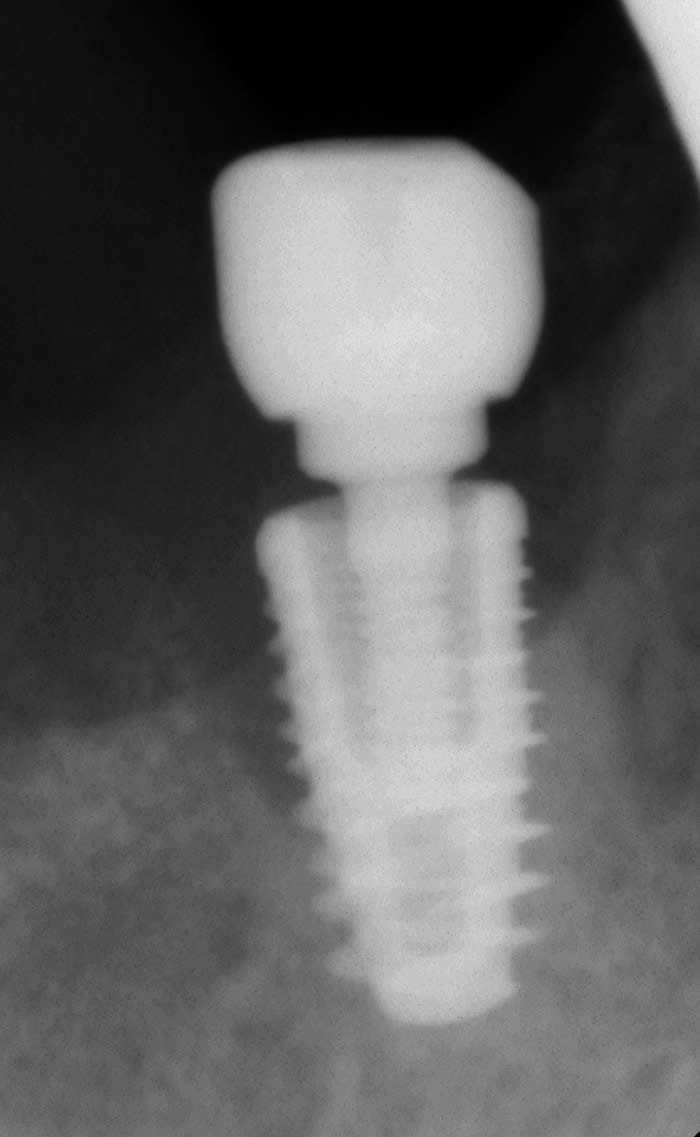

Nouveau sur le forum, je suis encore étudiant en 5e année, et aurai besoin de vos lumières pour l'identification de ces deux implants en place de 14 et 15.

nobel replace trilobe